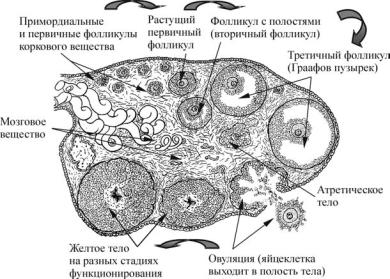

Созревание фолликула в яичнике: этапы и процессы